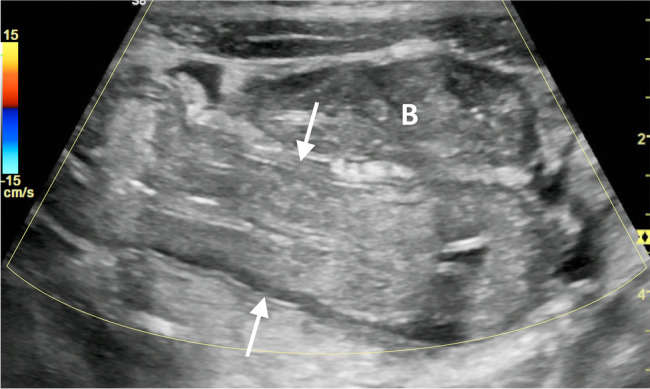

On US, the colitis appears as concentric mural thickening and partial loss of stratification, with notable avascularity in the acute prodromal stage caused by the thrombotic nature of the disease (Fig. 9). This is followed by bowel reperfusion and hypervascularity, by which time the renal and hematological features of the illness are apparent [32]. Recognition of the early avascular phase on US is especially important because colitis often precedes extra-intestinal manifestations, and initial clinical presentation might overlap with intussusception and other infectious and inflammatory diseases.

Fig. 9.

Hemolytic uremic syndrome in a 3-year-old boy presenting with bloody diarrhea, thrombocytopenia and renal failure after eating an undercooked hamburger. Transverse color Doppler US image of the rectosigmoid colon demonstrates marked circumferential mural thickening and partial loss of stratification without associated hypervascularity (arrows) during the initial avascular phase of the disease. Note the bladder (B), which is collapsed in the setting of oliguria